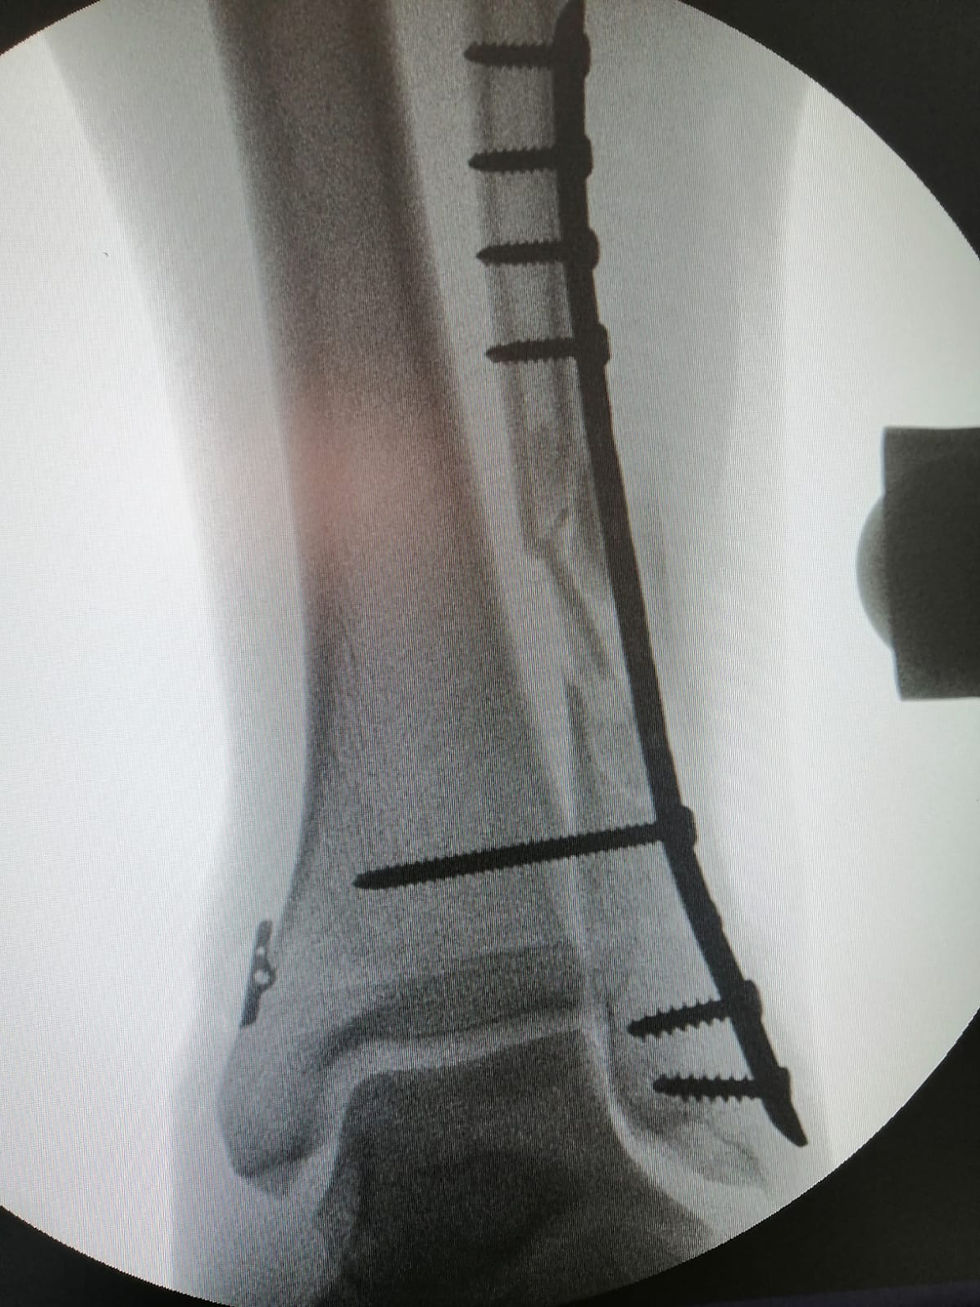

Sistema Placas para

Peroné

Placas anatómicas bloqueadas y de ángulo variable compatible con sistema de fijación sindesmal flexible.

El set incluye placas anatómicas o pre-formadas por lateral, antero-lateral y postero-lateral.